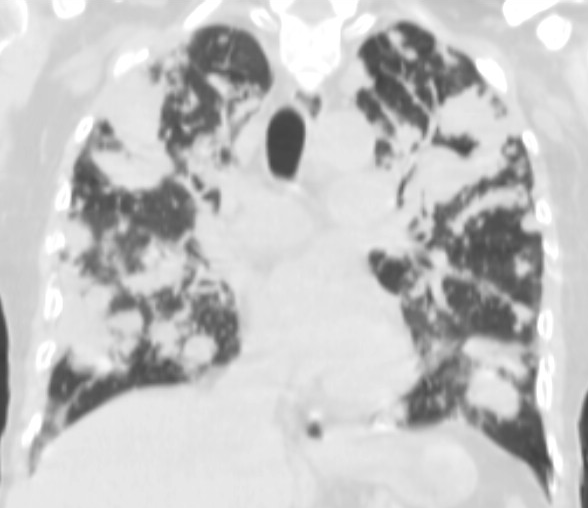

19. Tuberculosis, bidirectional chest radiographs and HRCT. (coronal reconstruction)

75 year old man: hx of hypertension, smoking. Symptoms: dyspnea, productive cough. Moist rales of auscultatory findings above the LLL, tension irritability in the level of lower dorsal spine.

a.) Chest radiograph, bilateral: Mild increased vascular markings. Extensive patchy lobar infiltration in the RUL Previous TB specific lesions in the left apex. The diaphragm contour is blurry on the right side (appr. 4 finger-wide pleural effusion). Cardiomegaly. Medium large dilated sclerotic aorta.

b.) HRCT: Reticular pattern of 10x10x5 cm area in the right apex (1st segment), (septal thickenings), mosaic-like ground glass opacity in the righ apex. Subpleural total atelectasis (mainly 1st segment): irregular mainly nodular soft tissue streak associated with the pleura (max. appr. 1 cm thickness). Some tiny subpleural emphysematous bullae in the right apex.